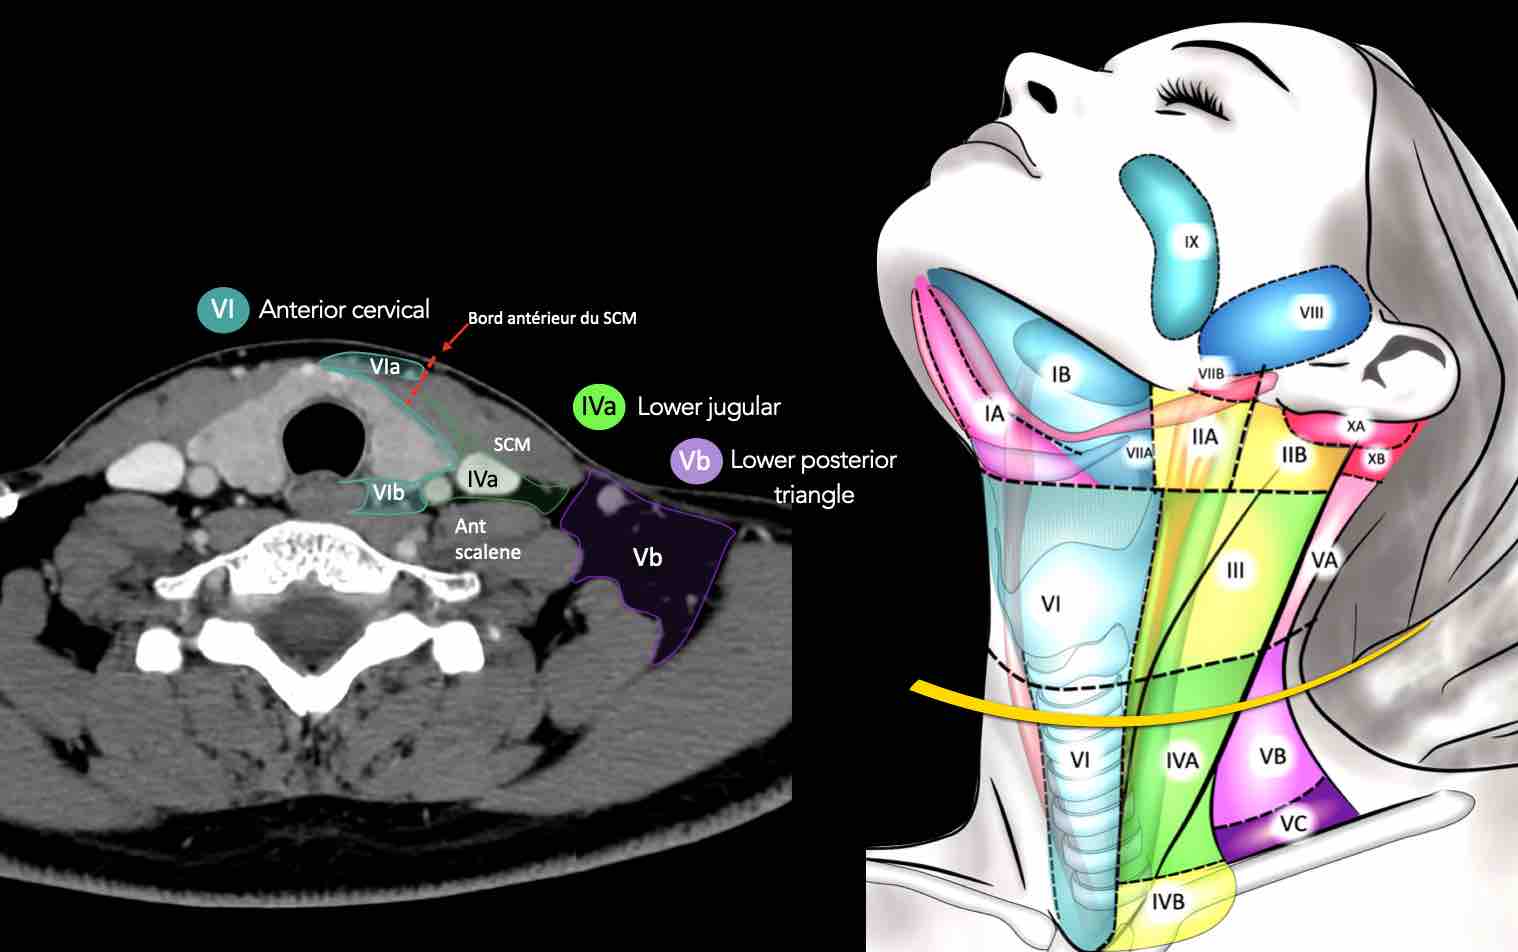

CT Scan Mặt Cắt Ngang (Axial CT)

Các lát cắt CT mặt phẳng ngang tương ứng với hình minh họa tổng quan.

Các lát cắt CT mặt phẳng ngang với hình ảnh chi tiết hơn.

Nhấp vào hình ảnh để phóng to.

IV – Tĩnh mạch cảnh dưới và hố thượng đòn trong

Ranh giới giữa tầng IVa và IVb được xác định tùy ý tại vị trí 2 cm phía trên khớp ức đòn.

Tầng IVa

Các hạch này có nguy cơ chứa di căn từ các ung thư hạ hầu, thanh quản, tuyến giáp và thực quản cổ.

Hiếm gặp hơn, di căn từ khoang miệng trước có thể biểu hiện tại vị trí này với tổn thương hạch gần tối thiểu hoặc không có.

Tầng IVb

Các hạch này có nguy cơ chứa di căn từ các ung thư hạ hầu, thanh quản dưới thanh môn, khí quản, tuyến giáp và thực quản cổ.

V – Tam giác cổ sau và hố thượng đòn

Tầng V chứa các hạch của nhóm tam giác cổ sau nằm ở phía sau cơ ức đòn chũm, xung quanh phần dưới của thần kinh phụ gai sống và các mạch máu cổ ngang.

Các hạch bạch huyết ở tầng V thường liên quan nhất đến các ung thư nguyên phát của vòm hầu, hầu miệng, các cấu trúc da vùng da đầu phía sau và tuyến giáp.

VI – Cổ trước

Tầng này chứa các hạch tĩnh mạch cảnh trước nông (tầng VIa) và các hạch sâu hơn bao gồm hạch trước thanh quản, trước khí quản, cạnh khí quản và hạch thần kinh thanh quản quặt ngược (tầng VIb).